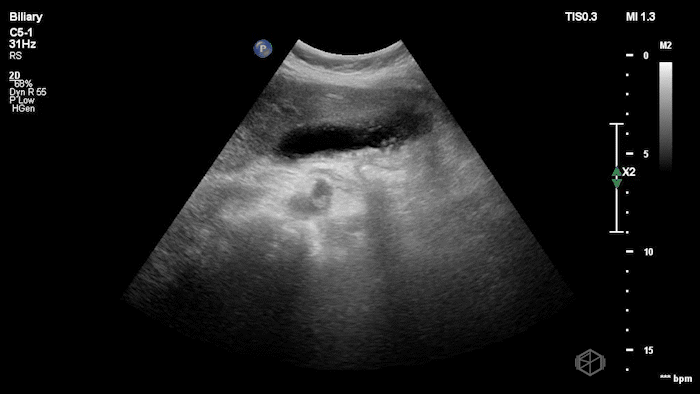

08 - What are the 6 signs of cholecystitis and what signs are visible here?

6 signs of cholecystitis — aGBW thickening >4mm, gallbladder wall edema, stone-in-neck (SIN) sign, pericholecystic fluid, hydropic gallbladder 10cm x 5cm, sonographic Murphy’s

Signs visible on this scan — SIN, hydropic gallbladder, gallbladder wall thickening

08A - The same patient above - what is the next procedure this patient needs and why?

ERCP - choledocholithiasis - stone present in bile duct.